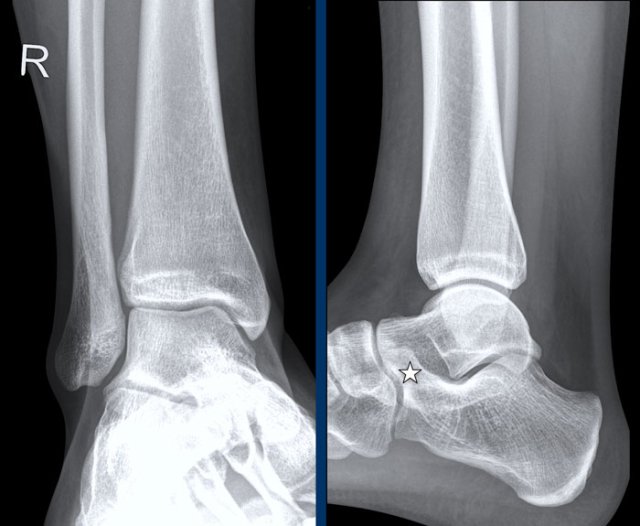

case 2 - distortion

In this case the most obvious finding is a fracture of the posterior malleolus.

This should urge you to look for other findings, since an isolated fracture of the posterior malleolus is extremely uncommon and probably does not exists.

You need to look at the algoritm for ankle fractures..

This means that we have to look for other signs.

Since there is no sign of a Weber B fracture, this must be a Weber C fracture.

Are there any other signs that are in favor of a Weber C fracure?

Yes there is.

Now we recognize the soft tissue swelling on the medial side and a small avulsion, which is stage 1 of this injury.

We now can predict a high fibula fracture, which was confirmed by a radiograph of the whole lower leg.